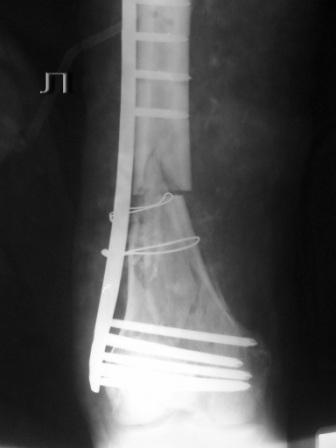

Пациенту 50 лет. 24.11.09 сделали л\бедро.

Оставлен клинически значимый варус, видно градусов 8-10. Для уточнения можно сделать снимок симметричного сегмента и скиаграммы наложить.

Не стоило открывать промежуточные отломки и вязать их проволокой. Это ухудшает их кровоснабжение и может привести к несращению. Не во все случаях, конечно. Удачи.

Сложность репозиции привела к "освобождению" промежуточных отломков - появился значительный костный дефект - пришлось создавать картинку + добавили коллапан.

В Вашем примере, как мне кажется, была довольно травматичная открытая реползиция со скелетированием концов перелома. В результате отсутствует необходимая биологическая составляющая для нормальной репарации кости. кроме того, положение отломков по оси - так себе, и имеется значимый медиалный дефект. Так что к био-логической мостовидной технике фиксации переломов этот случай не имеет никакого отношения. Увы(